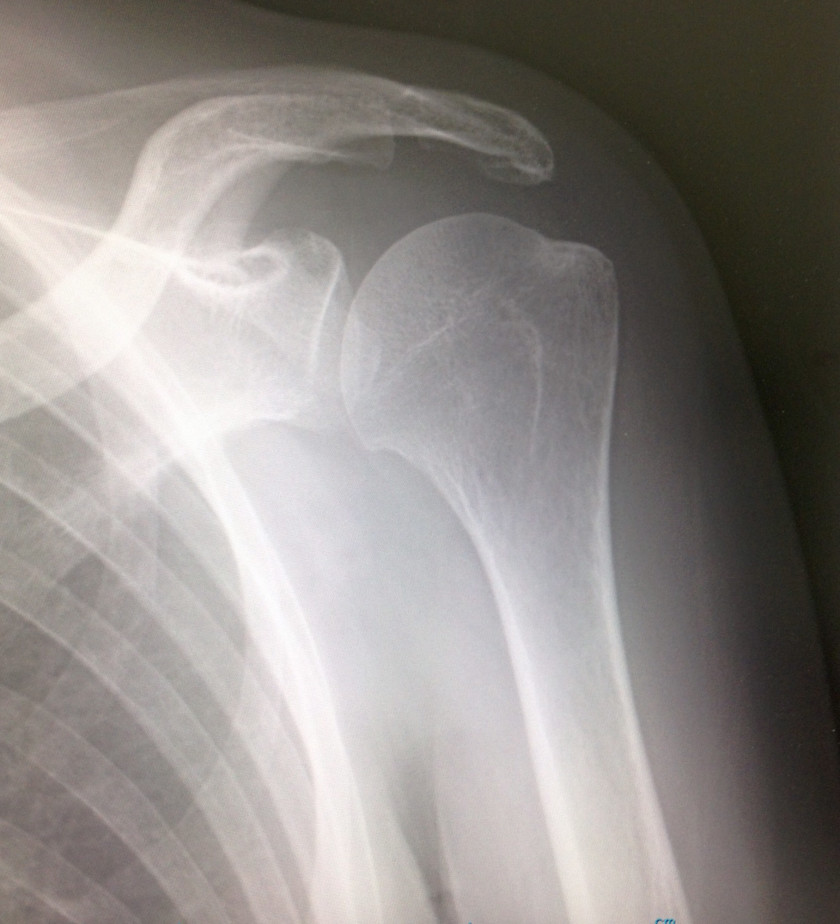

先月末に受診された、元気いっぱいの患者さん。昨年、関節の可動域制限を伴う左肩関節痛で近医を受診。『腱板断裂』と診断されました。以降、毎日❓通院され物理療法を受けるも症状は改善せず。

・・・で、知人の紹介もあり、先月末の当院受診となったワケです。

診断名を聞いて・・・所見を取り、レントゲンも見れば、ちゃいますね�。と容易にわかります。

診断は難しくなるので詳細は省略しますが、神経痛だったのですよ。で、治療開始して10日目。

痛みは5分の1になったそうです。良かった😊関節の可動域訓練も開始。

復活に向けて始動です‼️誤診はナニも認知症に限ったことじゃありません。